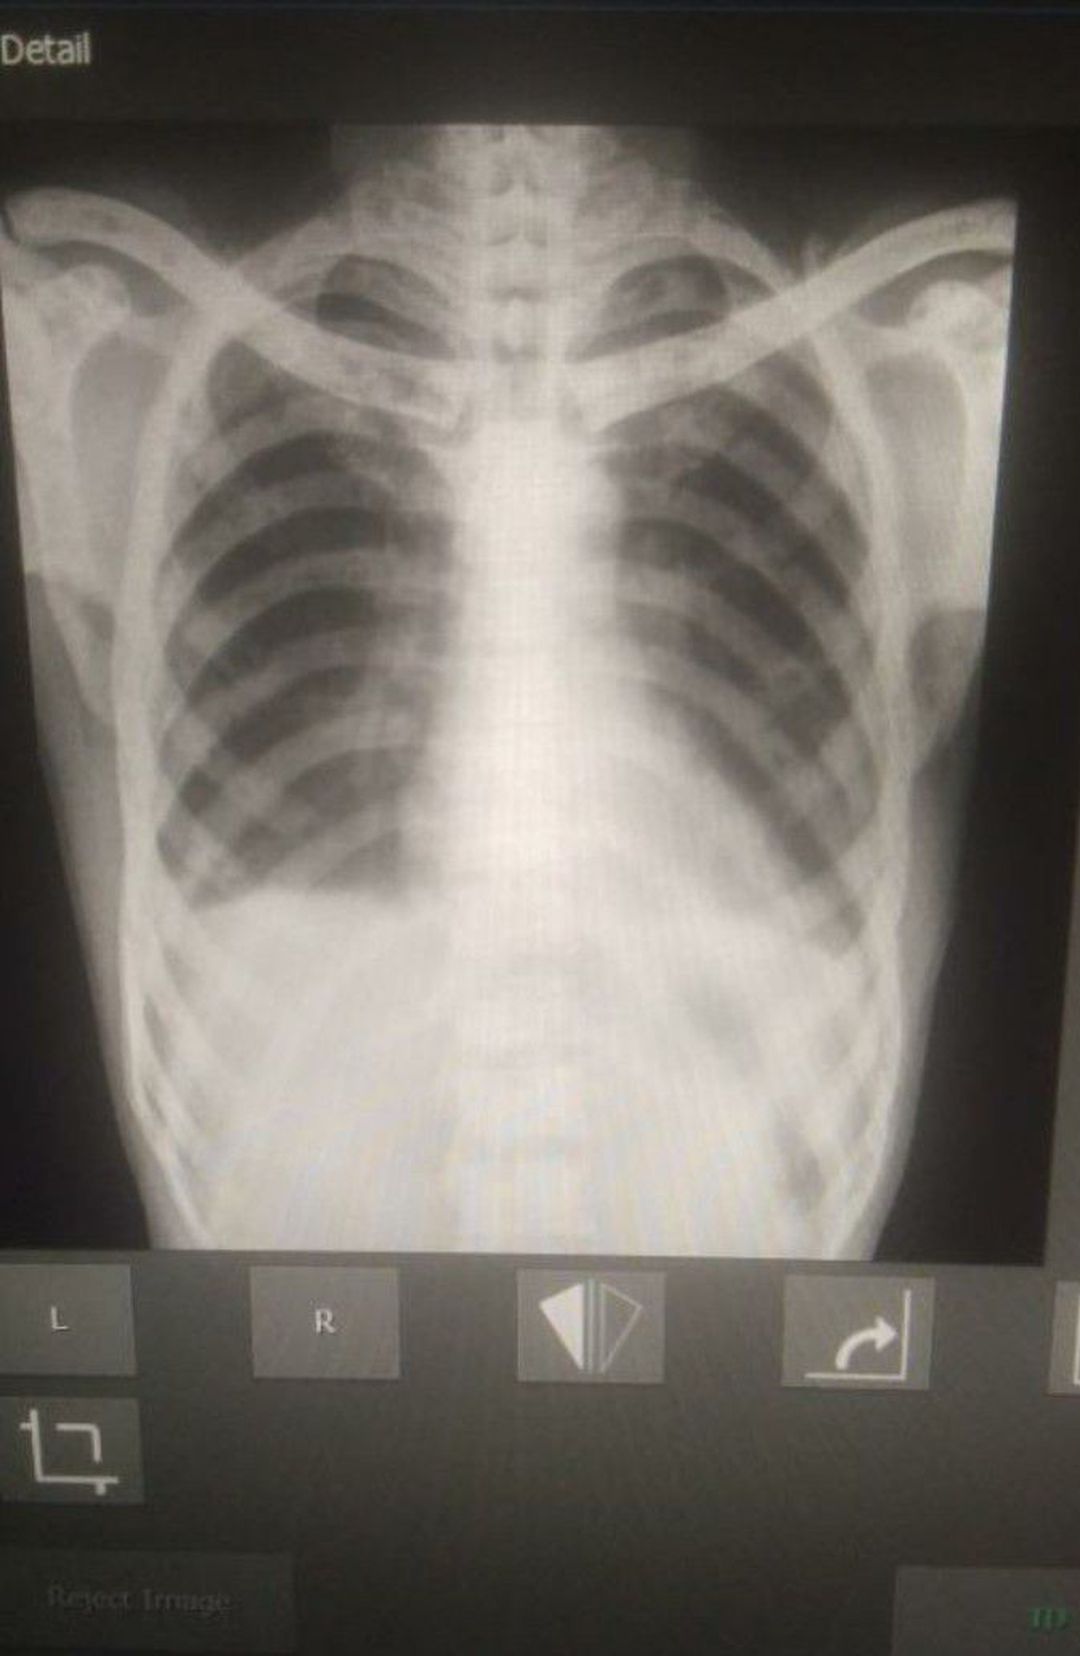

Frd pls help me to diagnosis....

Left pleural Effusion